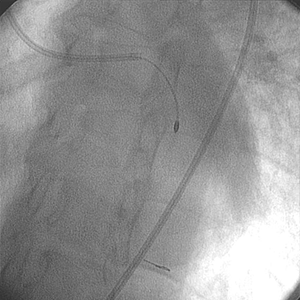

• The use of the Rotablator System facilitated the delivery and expansion of a 4.0 mm × 9.0 mm stent with good angiographic appearance

The Rotablator System served as a facilitator of lesion compliance and ultimately, stent delivery and expansion.

This case illustrates the ability of the Rotablator System to modify calcified atherosclerotic plaque in order to facilitate optimal stent delivery and expansion. Angiographic assessment did not uncover the calcified nature of the lesion.

After multiple balloon dilatation attempts with non-compliant balloons, the level and extent of calcification was made apparent. Although the 1.75 mm burr did not increase the lumen size, it did allow for subsequent expansion of the lesion by means of a PTCA balloon catheter and stent.